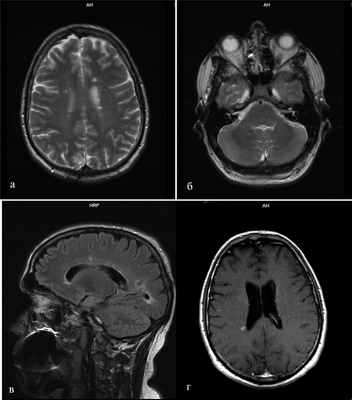

Лабораторные анализы крови и мочи были в норме. По результатам магнитно-резонансной томографии (МРТ) головного и спинного мозга были выявлены множественные очаги демиелинизации величиной 3-7 мм, гиперинтенсивные на Т2-взвешенных изображениях (Т2-ВИ) и гипоинтенсивные на Т1-взвешенных изображениях (Т1-ВИ), локализующиеся в белом веществе больших полушарий мозга, перивентрикулярных и подкорковых отделах, мозолистом теле. Аналогичный единичный очаг наблюдался в правом полушарии мозжечка (рис. 1). Рисунок 1. МРТ головного мозга. Множественные очаги демиелинизации, гиперинтенсивные на Т2-ВИ. a - локализующиеся в белом веществе больших полушарий мозга, перивентрикулярных и подкорковых отделах; б - аналогичный единичный очаг регистрируется в правом полушарии мозжечка; в - очаги перивентрикулярно и в мозолистом теле; г - МРТ через 3 мес, по сравнению с предшествующими результатами выявлено появление новых очагов демиелинизации; очаг у заднего рога правого бокового желудочка накапливает контрастное вещество.

Для верификации диссеминации патологического процесса во времени и установления достоверного диагноза РС пациенту было проведено повторное МРТ-исследование головного мозга через 3 мес. По сравнению с предшествующими результатами МРТ отмечалось появление новых очагов демиелинизации слева в перивентрикулярном отделе и у заднего рога правого бокового желудочка; при введении контраста последний очаг накапливал контрастное вещество (омнискан) (см. рис. 1). Согласно критериям Макдональда [13], пациенту был выставлен диагноз: РС, ремиттирующее течение. Через 3 мес гиперкинезов в руке выявлено не было.